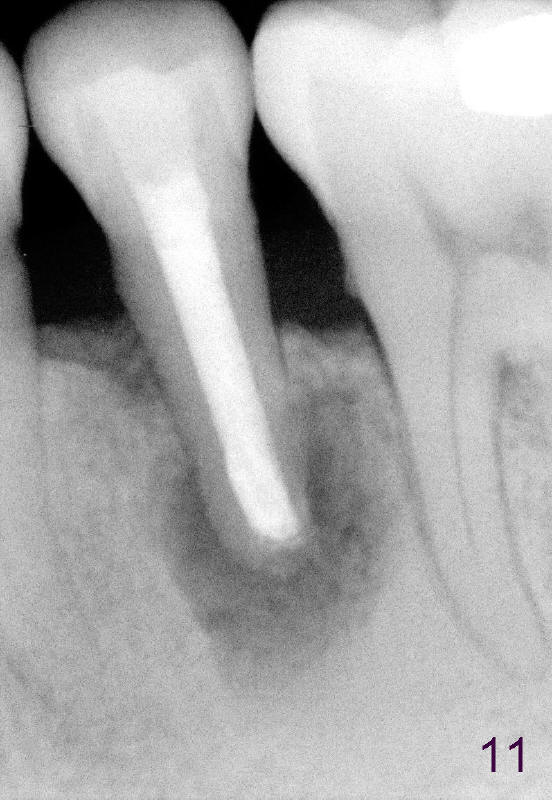

A 40-year-old Chinese man has periodic (once a month) mild pain and swelling in the lower left quadrant. Clinical exam reveals dens evaginatus (Fgi.1': <) in #20. Upon pressure from mouth mirror handle, there is limited amount of purulent discharge from the fistula (Fig.1": <). Preop PA shows a large canal with large periapical radiolucency (Fig.1). RCT started on Aug 6, 2010 with #70 file at 20 mm (Fig.2), #120 file at 16 mm (Fig.3) and CaOH paste in the canal (Fig.4). The dressing changed on Oct 8, 2010 (Fig.5). RCT finished on Jan 25, 2011 with master cone (rolled with several gutta perchae) (Fig.6), lateral condensation (Fig.7) and after vertical condensation and build-up (Fig.8). The canal was wet in the last two appointments with no sign of apexification. Follow up is done in 7 months (Fig.9), 11 months (Fig.10) and 18 months. Although the patient reports no pain after the treatment, the fistula remains with purulent discharge. The patient does not accept apical surgery. What should we do? Retreat with MTA (1,2,3)?